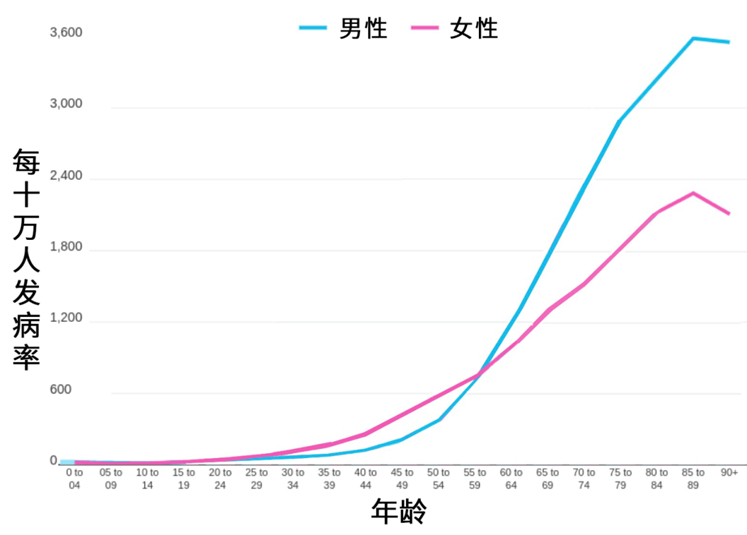

接下来,一个很好玩的问题——世界上癌症发病率最低的两个国家是哪两个?如果我告诉大家答案就是澳大利亚和新西兰。你相信吗?事实上,澳大利亚和新西兰是全世界癌症发病率最高的两个国家。为什么?大家能看到,发病率最高的这20个国家绝大多数都是发达国家,非常颠覆普通人对于这件事情的认知。

这其实有几个很重要原因,比如说,发达国家的饮食是更加的不健康。他们吃很多肉蛋奶类,这些东西过量了,对身体不是特别好;还有,澳大利亚、新西兰,包括西欧、美国人民,有一个特别坏的习惯——日光浴,所以在欧美最多的癌症就是皮肤癌。其实晒太阳补充的是维生素d,维生素d能促进钙的吸收,但是像西方那样裸晒就没必要;最后,发达国家的癌症多有个很重要的原因,就是得癌症最大的风险因素,不是环境污染,不是饮食,也不是你的生活习惯,而是活得太久。无论男女,随着年龄的增加,癌症发病率都是上升的,尤其到了55岁以后,是指数性的上升,所以你多活一年,得癌症的风险可能就比前面一年翻了一倍,这是非常正常的,当然它的绝对值还是没有那么高。以前皇帝不得癌症,我自己有一首打油诗——“皇帝癌症少,原因很好找,不是御医好,全靠死的早”。新中国成立之前,我们的人均寿命都是在30多岁,中国现在70岁以上的老人8000多万,所以癌症自然也就多了。世界范围也好,中国也好,随着人均预期寿命的大幅上升,癌症就会越来越多。